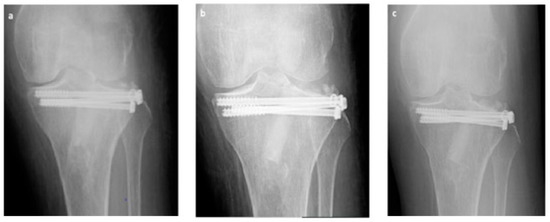

Figure 4. Exemplificative case, in anteroposterior RX, at 1 (a), 3 (b), and 6 (c) months follow-up respectively, well evidencing good consolidation, absence of non-union or retarded consolidation and graft good integration confirmed by progressive loss of radiolucency of the graft itself.

At each follow-up, we did not observe neither fracture recurrences nor radiographically noticeable subsidence or diastasis of the articular surface at follow up.

We did not detect pseudo-arthrosis, nor bone non-unions nor delayed consolidations [24]. Articular alignment was considered acceptable in all 34 cases at each evaluation (see also Figure 4).

At six months, X-rays images showed that all 34 fractures displayed a good consolidation rate, as confirmed by radiological reports. In particular, radiolucency of the xenografts was assessed [20], which became progressively more similar to that of the surrounding healthy bone tissue (see exemplificative Figure 1, Figure 2 and Figure 3 and comparative images in Figure 4).